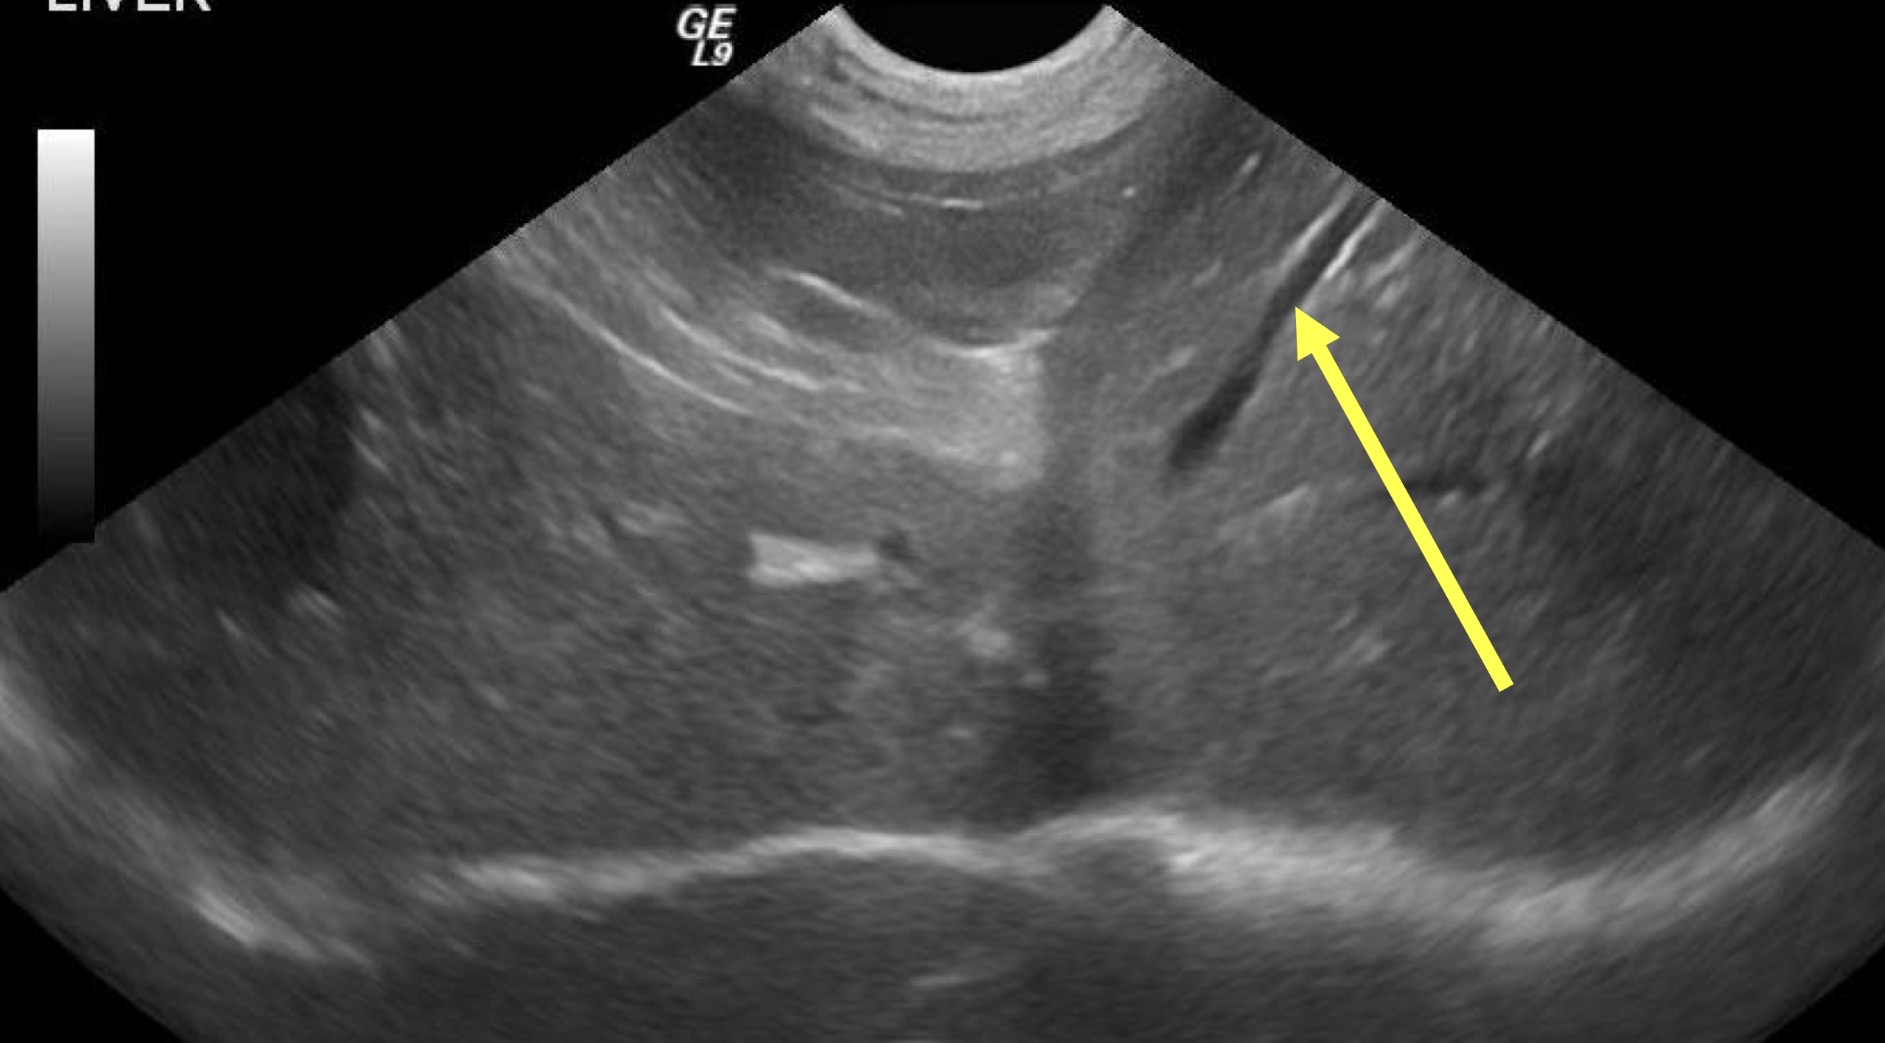

Portal veins

What structure is the yellow arrow pointing to ?